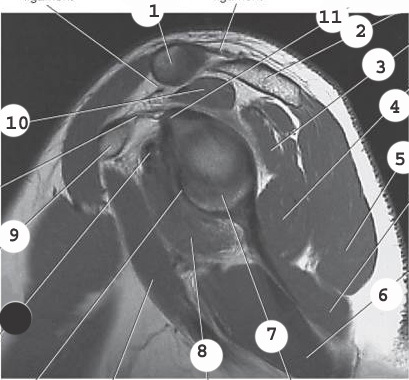

1

bicep

labrum

3

infraspinatus muscle

4

deltoid

2

acromion

8

subscapularis muscle

10

supraspinatus muscle